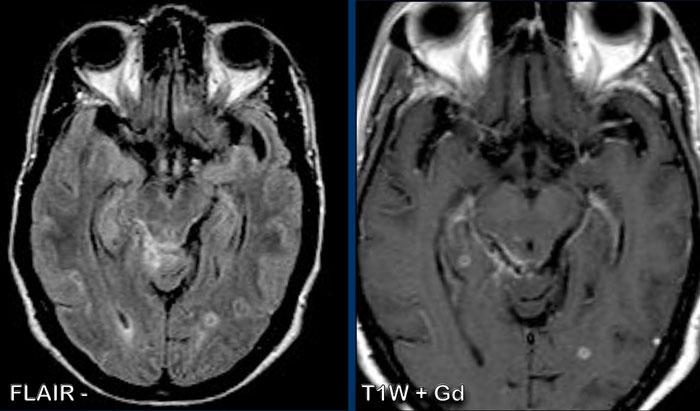

Đây là bệnh nhân ung thư phổi có biến chứng viêm màng não do ung thư.

Bạn có thể xác định những dây thần kinh sọ nào bị tổn thương không?

Trên các hình ảnh này rất khó nhận thấy, nhưng nếu bạn có thể cuộn qua các lát cắt MRI có tiêm thuốc, bạn sẽ nhận thấy các dây thần kinh sọ sau đây có ngấm thuốc bệnh lý:

- Dây III (mũi tên vàng)

- Dây V & dây VI (mũi tên cam)

- Dây VII & dây VIII (mũi tên xanh dương)

- Dây IX đến XI (mũi tên trắng)

Cũng lưu ý di căn tại cầu não.